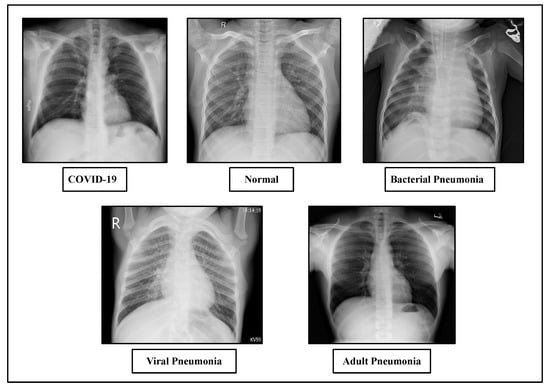

For our experiment, the dataset has been created from three different publicly available sources. The proposed dataset consists of a total number of 4593 chest X-ray images. To avoid the class imbalance problem, we have used a balanced dataset. First of all, the dataset includes 1143 chest X-ray images of COVID-19 patients collected from Kaggle’s repository “COVID-19 Radiography Database” provided by Tawsifur Rahman [76] and 1150 normal, 1150 bacterial pneumonia and 1150 viral pneumonia chest X-ray images from “Chest X-Ray Images (Pneumonia)” provided by Paul Mooney [77]. We have also collected some adult pneumonia dataset from kaggle’s repository “RSNA Pneumonia Detection Challenge” provided by the Radiological Society of North America [78]. We have used three datasets for our experiment: namely, Dataset-1, Dataset-2 and Dataset-3. Table 4 displays the Dataset-1 distribution for each subset with training and testing the data. In Dataset-1, for training purposes, we have used 60% dataset samples for training purposes and the remaining 40% samples are used for testing purposes. On the other hand, Table 5 shows the Dataset-2 distribution where 100% of the dataset samples are used for training and 40% of the data split from the training dataset is used for testing purposes. Figure 4 displays sample images of chest X-rays with different cases.

Figure 4.

Sample chest X-ray of COVID-19, normal, viral pneumonia, bacterial pneumonia and adult pneumonia cases.